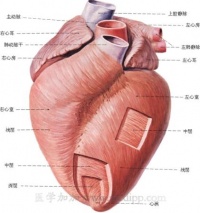

心肌(cardiac muscle) 由心肌细胞构成的一种肌肉组织。广义的心肌细胞包括组成窦房结、房内束、房室交界部、房室束(即希斯束)和浦肯野纤维等的特殊分化了的心肌细胞,以及一般的心房肌和心室肌工作细胞。前5种组成了心脏起搏传导系统,它们所含肌原纤维极少,或根本没有,因此均无收缩功能;但是,它们具有自律性和传导性,是心脏自律性活动的功能基础;后两种具收缩性,是心脏舒缩活动的功能基础。

心肌细胞具有传导兴奋的特性。正常心脏的节律起搏点是窦房结,它所产生的自动节律性兴奋,可依次通过心脏的起搏传导系统,而先后传到心房肌和心室肌的工作细胞,使心房和心室依次产生节律性的收缩活动。心肌的兴奋在窦房结内传导的速度较慢,约0.05米/秒;房内束的传导速度较快,为1.0~1.2米/秒;房室交界部的结区的传导速度最慢,仅有0.02~0.05米/秒;房室束及其左右分枝的浦肯野纤维的传导速度最快,分别为1.2~2.0及2.0~4.0米/秒。

1.正常情况下,窦房结的自律性最高,它自动产生的兴奋依次激动心房肌、房室交界、房室束及其分支和心室肌,引起整个心脏兴奋和收缩。由于窦房结是正常心脏兴奋的发源地,又是统一整个心脏兴奋和收缩节律的中心,故称为心脏的正常起搏点。故由窦房结控制的心跳节律,称为窦性节律。而正常情况下,窦房结以外的心脏自律组织因受窦房结兴奋的控制,不表现其自律性,故称为潜在起搏点。